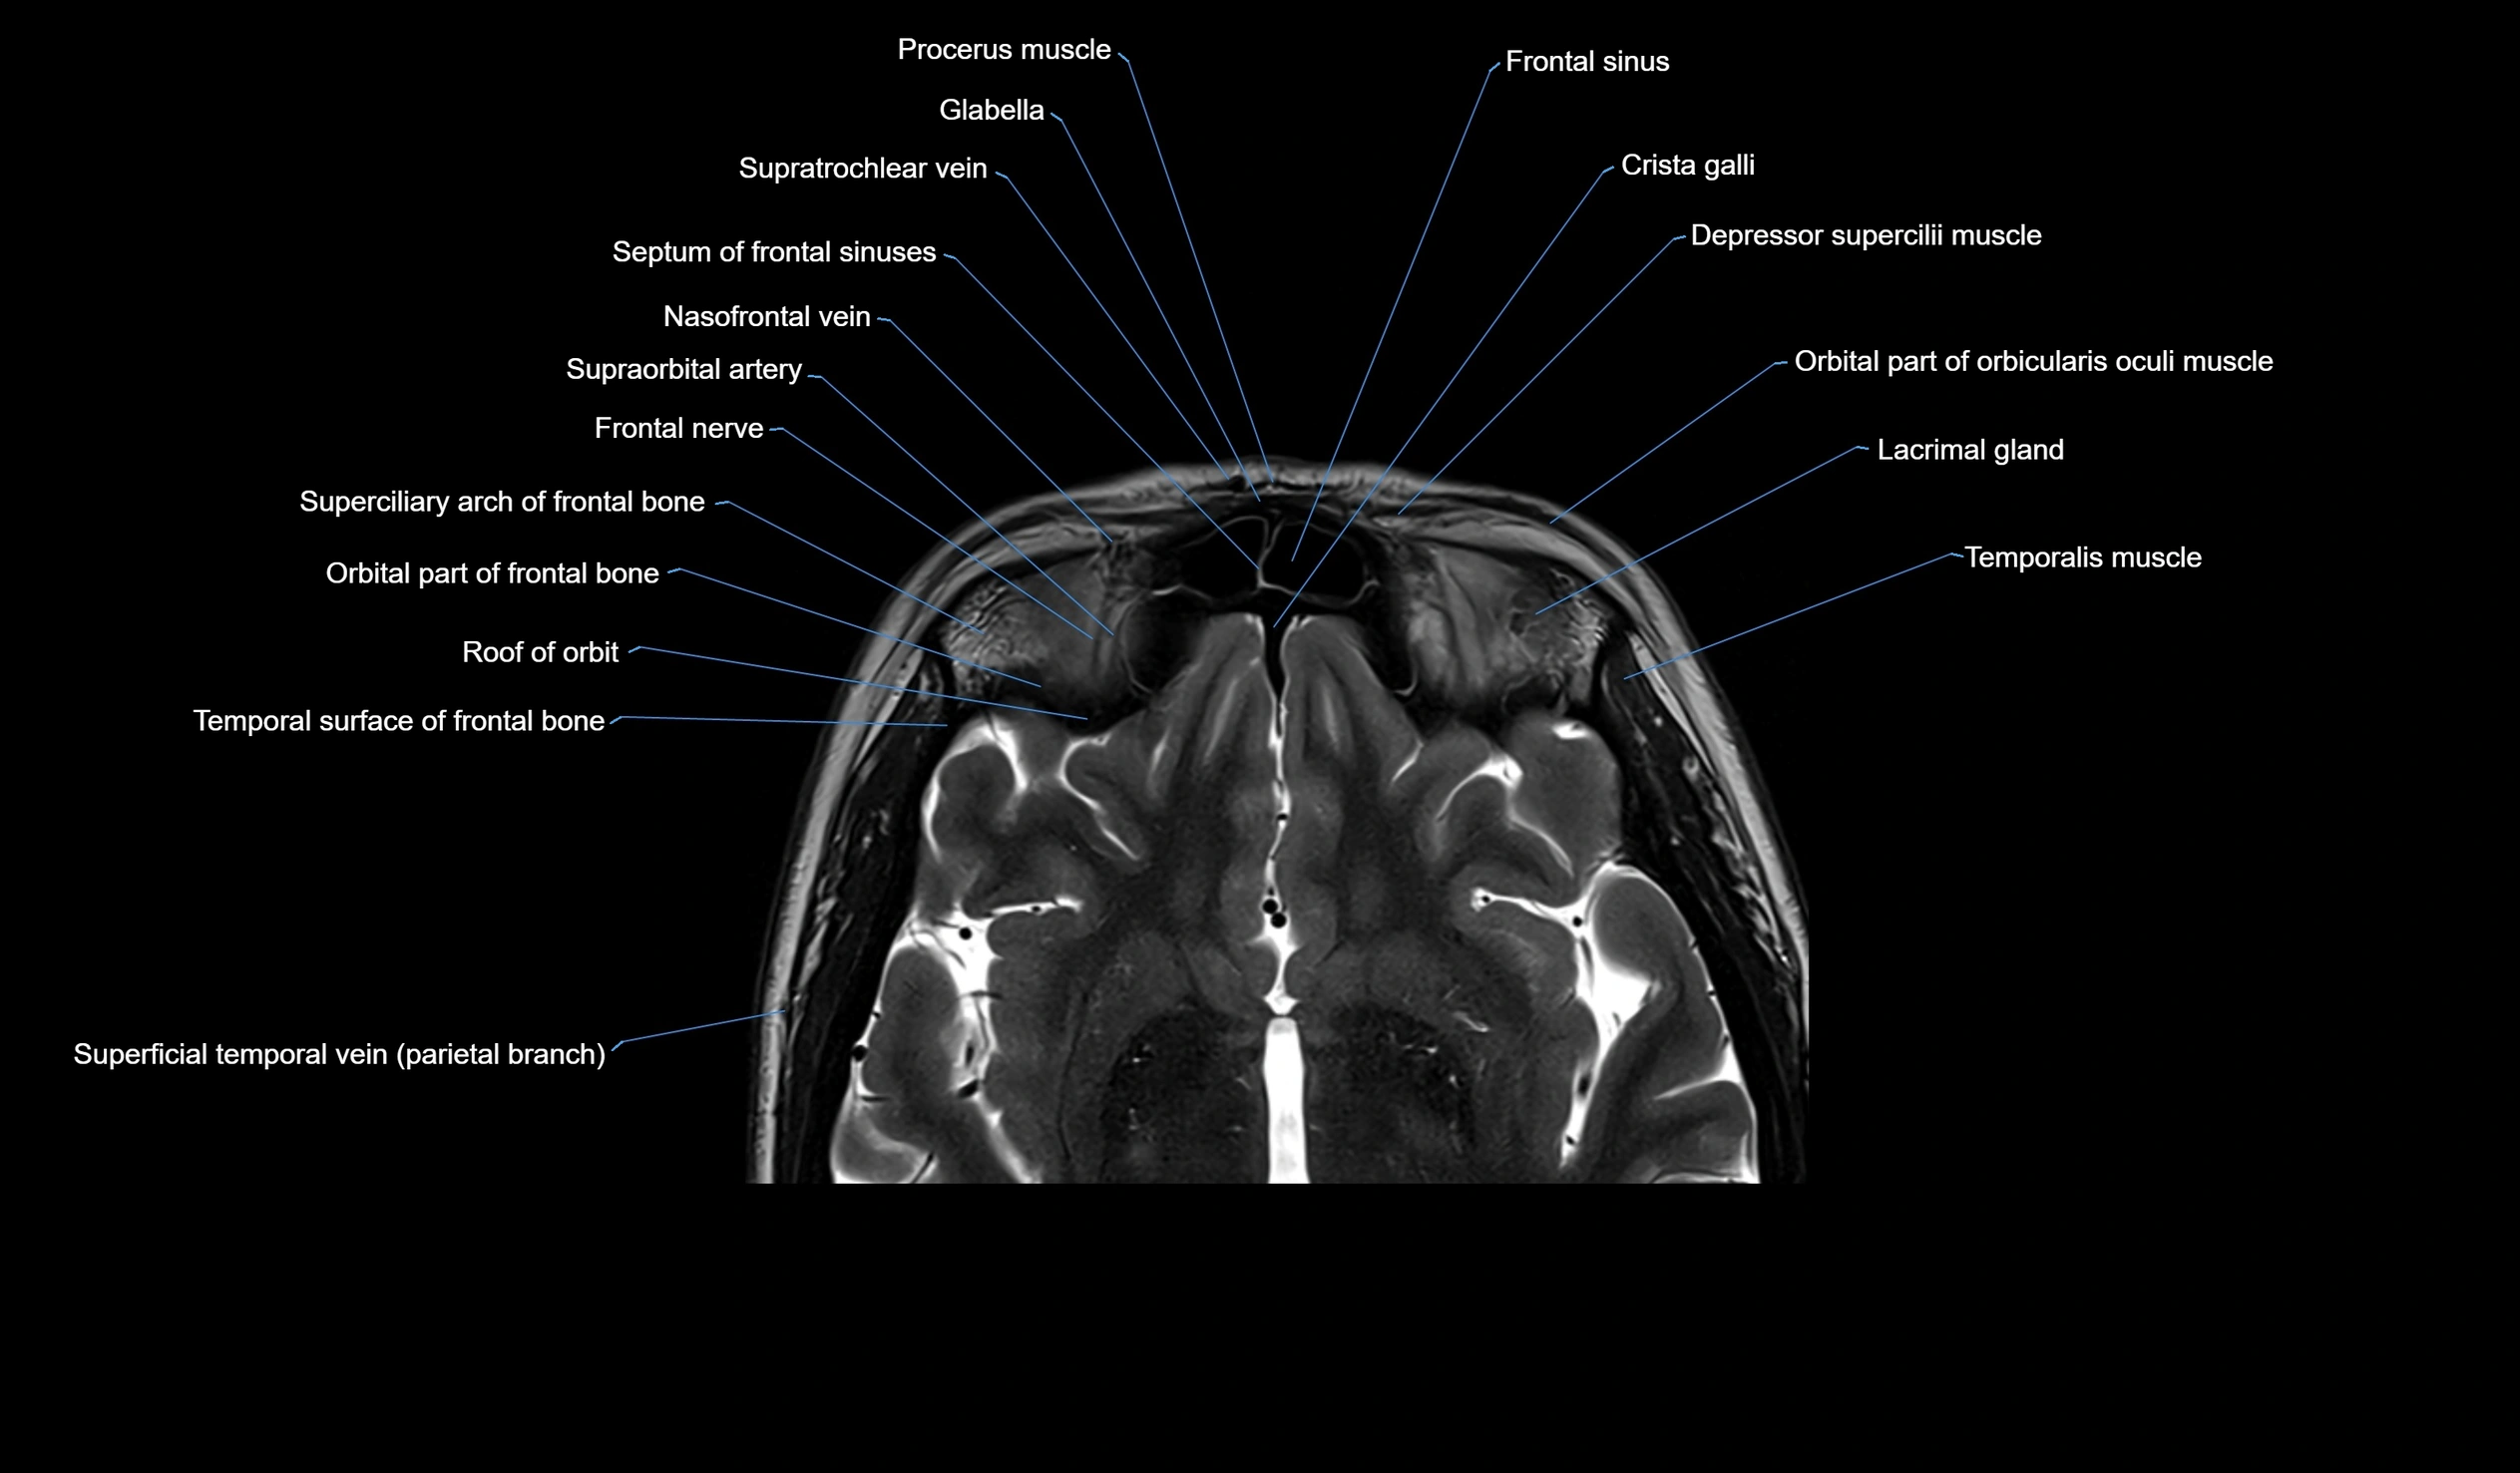

MRI images